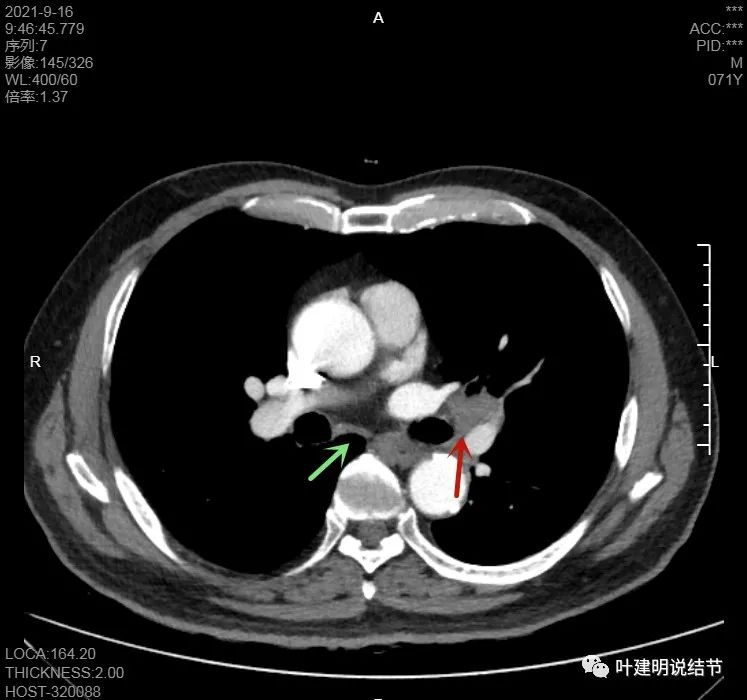

左下病灶在增强CT中强化不明显,但有肺门区肿大淋巴结,而且近3厘米大。同事叫我看片子的时候,本来只先看左下病灶处,以为是良性结节。但翻到肺门区,发现有如此大的肿大淋巴结,那这个原发灶则肯定是恶性的了!我们先来看纵隔窗的淋巴结情况:

左肺门区淋巴结肿大

肺门区淋巴结挤压附近肺血管,但似乎示见肿瘤侵犯破坏血管壁

淋巴结巨大,部分包绕肺血管,但仍未见明显侵犯血管壁

肺血管受压明显,气管内壁感觉也是光滑的

以上诸图均示肿大淋巴结挤压肺血管,但未见确切侵犯破坏,支气管内壁也感觉是光滑的,没有肿瘤突向管腔